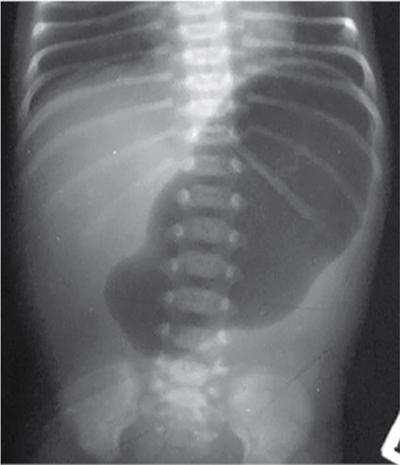

C.V. Kanimozhi, S. Muralinath, Raveendran J. Many of the important congenital gastrointestinal abnormalities present acutely in the newborn; some present much later. These include obstructive gastrointestinal lesions that present with vomiting, abdominal distension and not having passed meconium. The imaging modalities that are most commonly used in the evaluation of neonatal gastrointestinal abnormalities are plain films, contrast studies and ultrasound. Plain films remain a valuable tool in the assessment of abdominal abnormalities in the neonate. They are also an excellent guide to determining the next proper imaging study to perform for a particular problem. Certain neonatal bowel disorders have a pathognomonic appearance on radiographs obviating the need for further imaging. The essential and basic view to be done at the bedside is the supine view of the abdomen. In the evaluation of abnormal intra-abdominal gas patterns, alternative decubitus views, prone and supine cross-table lateral views may be taken. Erect view is not utilized in neonatal practice at the bedside as it is impossible to restrain a neonate in that position and unnecessarily subjects the neonate to stress, which may worsen the condition of an already sick baby. Evaluation of the bowel gas pattern and the anatomic localization of the intra-abdominal gas is the key to diagnosis in the evaluation of diseases of the GI tract. The bowel gas in the neonate is essentially swallowed air (Box 7.8.1). Movement of Air Through the GIT in a Term Neonate Most infants pass meconium by 24 hours of life. In order to interpret the bowel gas pattern and determine if an abnormality is present, it is crucial to know the age of the neonate (hours since birth) at the time the radiograph was taken. When there is impaired swallowing, such as due to CNS depression or in prematurity, radiographs show diminished bowel gas. In cases of bowel atresia, radiographs show absence of bowel gas in distal segments. Thus, the distribution of bowel gas and its pattern serve as pointers to the diagnosis. After the radiograph has been done, depending on the findings, an ultrasound or fluoroscopic contrast study may be performed next. The radiologist should tailor the contrast study to suit the particular patient and the clinical question that needs to be answered. In cases of suspected high GI obstruction, an upper GI contrast series is study of choice; in cases of suspected low GI obstruction a contrast enema should be performed to delineate the anatomy. When performing fluoroscopic studies, it is important to bear in mind the radiation dose and to adopt the ALARA principle. Minimizing radiation exposure in children is important because they are more sensitive to the effects of radiation and have a longer life expectancy than adults. The technical parameters must be adapted to paediatric imaging. Ultrasound is a useful bedside tool particularly in the sick neonate. In neonates, the sonographic image resolution is excellent due to the lack of significant body fat. In neonates, exquisite images of the abdomen can be obtained with the high-resolution ultrasound probe, which permits imaging the bowel wall in great detail. In addition, it can also reveal other causes for abdominal distension or vomiting. In this chapter, we will discuss the aetiology, clinical presentation and imaging appearances of congenital neonatal gastrointestinal abnormalities. We will also discuss common acquired abnormalities that present in the neonatal period, namely necrotizing enterocolitis. Congenital oesophageal malformations of the newborn include the various types of atresia (with and without fistula) and oesophageal duplications. Oesophageal atresia with or without tracheoesophageal fistula (TEF) is a common congenital anomaly that manifests in the neonatal period. It is also the most important congenital malformation of the oesophagus. Oesophageal atresia is commonly associated with other anomalies of the gastrointestinal tract such as imperforate anus, pyloric atresia, duodenal atresia and annular pancreas and less frequently with anomalies of the cardiac and genitourinary systems. About 20% of patients with oesophageal atresia have the VACTERL syndrome (vertebral anomaly, anorectal atresia, cardiac lesion, tracheoesophageal fistula, renal anomaly, limb defect). Oesophageal stenosis and webs may be associated with oesophageal atresia. The aetiology of oesophageal atresia and TEF is not completely understood. Faulty separation of the primitive trachea and oesophagus is the most widely accepted theory. The way the primitive foregut cleaves into a ventral (tracheal) passage and a dorsal (oesophageal) passage is a complex process and is poorly understood. Folds developing from the longitudinal ridge is said to separate the two. When the separation has an extreme tracheal bias, an oesophageal atresia occurs and if the bias is towards the oesophagus, then a tracheal atresia ensues. Incomplete separation may result in fistula of various types. Oesophageal atresia and TEF are classified depending upon the absence or presence and location of the fistula between the oesophagus and the trachea (Fig. 7.8.1). Neonates present within a few hours of birth with excessive salivation, drooling, cyanotic spells and regurgitation of feeds. The inability to successfully pass a nasogastric tube strongly suggests oesophageal atresia. Newborns with H-type fistula may have feeding difficulties and choking, but often the presentation and diagnosis is only later in infancy when the patient presents with cough, choking episodes and recurrent pneumonia. The role of imaging is to diagnose, define the anatomy to the best extent possible and evaluate for other anomalies to provide a clear picture for the paediatric surgeon. For example, it is important for the surgeon to know the side of the aortic arch in order to lateralize the surgical approach. Chest X-ray and Echo can localize the arch and determine if an anomalous right-sided aortic arch is present. Plain films of the chest including abdomen need to be obtained. The radiograph will demonstrate the air-filled distended proximal oesophageal pouch. If a nasogastric tube has been inserted, the coiled tube will be seen within the pouch. Absence of bowel gas in the abdomen indicates oesophageal atresia without a distal fistula – types A and B have this radiographic appearance (Fig. 7.8.2). The presence of gas in the gastrointestinal tract indicates the presence of a distal fistula – types C and D (Fig. 7.8.3). Contrast studies to delineate the proximal pouch are generally not indicated. Coiling of the nasogastric tube in the proximal pouch confirms the diagnosis. Chest radiographs frequently show changes of consolidation due to aspiration pneumonia, most often involving the right upper lobe (Fig. 7.8.4). In cases of H-type fistula, plain films are nonspecific and the diagnosis depends on contrast studies. Radiological diagnosis is made by means of a tube oesophagogram. This study has the potential risk of aspiration and the neonate may desaturate quite rapidly. Hence, it is important to have neonatal emergency resuscitation at hand. The tube oesophagogram is performed under fluoroscopy with the baby in lateral- or steep-prone oblique position. The NG tube is placed at the oesophagogastric junction and is gradually withdrawn while simultaneously injecting contrast. Nonionic low-osmolar contrast agent should be used. Most of the H-type fistulas are located in the lower cervical and upper thoracic regions with the fistula typically coursing upward and forward from the oesophagus. In the presence of a fistula, the contrast will be seen passing into the trachea in an upwardly oblique configuration. Aspiration during the study can also cause the contrast to appear in the tracheal tree and the lungs. It needs to be established whether the contrast has passed through the fistula or whether aspiration has occurred. Recording of the fluoroscopic run and reviewing the images may be required to make this distinction. Repeat examination may be required. Demonstration of H-type fistula can be difficult radiologically. In such patients, bronchoscopy with transfistula guidewire placement has been found to be of use. MRI – High resolution structural MRI is a new technique that is being used to visualize tracheobronchial anatomy. The disadvantage with radiographs is that one cannot determine the anatomic subtype of TEF, the site of the TEF or the length of the gap between the atretic segments. Using ultrashort echotime (UTE) MR imaging, it is possible to visualize the exact site of the fistula and assess the size of the oesophageal gap. This can aid presurgical planning and help identify infants at risk for complications, such as those with a long oesophageal gap. Imaging plays an important role in the evaluation of early and late complications of atresia repair. Early complications include anastomotic leaks and are seen in about 10%–20% of cases. Oesophageal contrast study, using a nonionic low-osmolar contrast agent, is performed to demonstrate the leak at the anastomotic site (Fig. 7.8.5). Leaks are associated with a greater incidence of subsequent stricture development. Anastomotic stricture is a common complication seen in about 30%–40% of cases. Often there is a slight narrowing at the site of repair without the patient having any difficulty in swallowing (Fig. 7.8.6). The anastomotic narrowing is clinically relevant only if the patient has dysphagia; such cases respond to dilatations. Recurrent TEF occurs in 5%–10% of cases after oesophageal atresia repair. Late complications include dysphagia, gastroesophageal reflux, tracheomalacia and chest wall deformities. Dysphagia can occur post-operatively due to abnormal oesophageal motility. Oesophageal dysmotility can be caused by abnormal neural development of the oesophagus or may result from complication of atresia repair. Gastroesophageal reflux affects 40%–65% of patients following oesophageal repair. It may be due to an intrinsic deficiency in the motor function of the oesophagus; this may get exacerbated postrepair due to an alteration of the anatomical gastroesophageal junction. Oesophageal atresia key imaging finding – X-ray shows NG tube coiled in proximal oesophageal pouch. The stomach is divided into the fundus and body proximally and the antrum distally. The antrum is divided by the sulcus intermedius into a proximal pyloric vestibule and a distal pyloric antrum or pyloric canal. This canal terminates into the pyloric sphincter beyond which is the duodenum. Congenital anomalies of the stomach that manifest in the neonatal period are uncommon. Hypertrophic pyloric stenosis (HPS) is the most common surgical cause of vomiting in infants. The incidence is 2–5 per 1000 live births, with geographic and racial variations. Compared to Caucasians, HPS is less common amongst Asian populations. The male to female ratio is approximately 4:1, occurring more commonly in the first-born child. The precise aetiology is unknown. Overactivity or prolonged spasm of the circular muscle of the pyloric antrum is thought to be the primary problem in these infants. This spasm leads to muscle hypertrophy and obstruction. Multiple hypotheses have been proposed for this prolonged spasm. One is that some infants are genetically predisposed to increased gastrin production which leads to a vicious cycle of hyperacidity, increased gastric contraction and secondary development of muscular hypertrophy. Most infants present after the first week of life and before 3–4 months of age. Typical symptoms include projectile nonbilious vomiting, regurgitation and difficulty in feeding. The gastric outlet obstruction can lead to emaciation. The distended stomach with active peristaltic activity may be visible through the thin abdominal wall. In the past barium upper GI series was the mainstay diagnostic tool for HPS. Prior to the barium study, the stomach may need to be decompressed via a nasogastric tube. The classic sign on a barium study is the ‘string sign’ (Fig. 7.8.7) produced by a thin stream of barium in an elongated narrowed pyloric canal; the canal typically curves upward. In severe cases, complete obstruction will lead to the ‘beak sign’, which is produced by beaking of the contrast as it enters the pyloric canal. With lesser degrees of obstruction, the ‘double track sign’ is seen. This is produced when the pyloric canal is flattened and the barium accumulates in the crevices along either side of the flattened canal. Pylorospasm can transiently mimic the findings of HPS. Currently, ultrasound is the modality of choice for the diagnosis of HPS and upper GI studies are seldom used. Ultrasound is considered the ‘gold standard’ as it allows direct examination of the pyloric muscle and also provides the ability to perform a dynamic study. The ultrasound examination is performed with a linear high-frequency transducer (6–10 MHz). The examination begins with the baby in supine position. First, the antropyloric region is identified; the pylorus is usually located medial and posterior to the gall bladder. The normal pyloric muscle is a thin hypoechoic layer that measures 2 mm or less. The abnormal pyloric canal shows thickening of the muscle and the mucosa to varying degrees. In cross section, it is seen as a hypoechoic structure likened to a doughnut. The length of the canal is measured in long section where its appearance is likened to the cervix. The sonographic diagnostic criteria for HPS are a thickened muscle layer measuring ≥3 mm and an elongated pyloric channel ≥15 mm (Fig. 7.8.8). The diameter of the pylorus in cross section was also one of the originally used measurements. However, due to a significant overlap between normal and abnormal, this measurement is no longer utilized. Additional ultrasound findings of HPS are hypertrophy of the pyloric mucosa and a distended, actively peristalsing stomach. The hypertrophied redundant mucosa projects into the antrum analogous to the ‘nipple sign’ in barium studies (Fig. 7.8.8D.). Colour Doppler imaging shows increased flow in the muscle and mucosa. The above-described measurements of pyloric muscle thickness and canal length are vital to diagnosis. However, dynamic assessment is equally important. One must evaluate the antropyloric region over a period of time to ensure persistent stenosis without evidence of relaxation and opening of the canal. A distensible antropyloric region with normal passage of gastric contents excludes HPS. Transient contractions of the pylorus or pylorospasm can mimic pyloric stenosis in both measurement and appearance. With observation over a period of time, opening of the pyloric canal may be visualized. Hence the key to diagnosis of HPS is persistent non-relaxing thickened musculature. Gas in the stomach may obscure the pylorus. To avoid this, place the infant in an oblique position, right side down which will allow the antrum to fill with fluid. Conversely, an overdistended fluid-filled stomach can displace the pylorus dorsally. In such cases, turning the infant left side down will displace the fluid towards the fundus and will allow the pylorus to rise to a more anterior position. At times, equivocal examinations may occur where the muscle measures 2–3 mm in thickness and does not relax. In these patients, careful monitoring with repeat ultrasound is warranted. In a few cases, the abnormalities advance overtime to fully developed HPS. Hence in such equivocal cases if vomiting continues, follow-up ultrasound is advisable. Surgical pyloromyotomy is the treatment for HPS. On ultrasound, the myotomy site can be seen as an interruption in the hypoechoic doughnut. It is important to be aware that postsurgery, the pyloric muscle may remain thickened for up to 5 months with a gradual return to normal thickness. In the first week after surgery, the muscle can be the same thickness as pre-op or even thicker. One should not be alarmed by this appearance. The dimensions gradually return to normal over the course of a few months. Postop if the child is thriving well, there is no need for imaging to be performed. HPS key imaging finding: On high-frequency ultrasound muscle thickness ≥3 mm and elongated pyloric channel ≥15 mm. Pyloric atresia is a rare anomaly comprising less than 1% of all intestinal atresias. Pyloric atresia is classified into three types (Fig. 7.8.9): The exact aetiology remains controversial. In the past, it was postulated that failure of recanalization of the gastrointestinal tract was the cause. Recent evidence suggests that pyloric atresia is the result of localized vascular occlusion. This vascular theory suggests that the atresia is due to focal ischemia secondary to intrauterine stress, vascular insult or anoxia. In complete obstruction, the presentation is in the neonatal period with nonbilious vomiting within the first few hours of life. Incomplete obstruction due to a diaphragm has a variable presentation depending on the size of the orifice. These patients can present later in life with intermittent vomiting or postprandial vomiting. In complete pyloric atresia, a dilated stomach is present on radiographs with absence of gas in the distal bowel. This is known as ‘single bubble’ appearance (Fig. 7.8.10). This appearance is diagnostic and in such cases, contrast studies are generally not required. In the membranous type, there is an opening in the centre of the diaphragm and hence, the obstruction is usually incomplete. On radiographs, the stomach is distended and lesser than normal volumes of air is present in the small bowel (Fig. 7.8.11). On upper GI barium studies, a diaphragm is seen as a thin (2–4 mm) linear filling defect that spans across the antrum with a normal pyloric canal. One needs to determine on fluoroscopy whether the membrane is causing significant obstruction or not. If obstructing, the diaphragm will balloon out with gastric peristalsis. In incompletely obstructing diaphragms, the edges of the diaphragm will be visible but there will no obstruction or ballooning. Pyloric atresia key imaging finding: X-ray abdomen – ‘single bubble’ appearance. Microgastria is an extremely rare congenital abnormality wherein the stomach is small, midline in position and typically associated with a dilated oesophagus. The stomach is represented by a small tubular structure without recognizable differentiation into fundus, body, antrum and pylorus. Agastria is the most extreme form of microgastria. Microgastria is frequently associated with other anomalies such as polysplenia-asplenia syndrome, malrotation, gastrointestinal atresia and vertebral, cardiac, renal and limb reduction anomalies (VACTREL association). Microgastria occurs due to arrest in early development of the foregut. In the 5th week of gestation, dilatation of the region of the future stomach occurs. Ninety-degree rotation of the stomach occurs in the 6th week, followed by development of the greater and lesser curves and growth of the fundus in the subsequent weeks. Arrest of this process leads to microgastria, with severity dependent on the stage at which arrest occurs. The development of spleen within the dorsal mesogastrium of stomach explains the association of microgastria and splenic anomalies. The association of limb, cardiac, tracheoesophageal, vertebral and renal anomalies has been attributed to impairment of early mesodermal development. The symptoms are related to the effects of the inadequate stomach and dilated oesophagus or due to the associated severe anomalies. These babies may present with feeding difficulties, failure to thrive, vomiting, recurrent aspiration and malnutrition due to severe gastroesophageal reflux. Radiographs may show an absent stomach bubble; in some cases, the shadow of the dilated oesophagus may be seen in the lower chest. On an upper GI study, the stomach appears small, tubular and midline in position. There is often associated severe gastroesophageal reflux and a very dilated oesophagus. The oesophagus dilates to take over the storage function of the inadequate stomach. Additional imaging studies are required to identify the associated anomalies. Key imaging finding: Upper GI study – Small, tubular stomach located in the midline. Congenital anomalies of the duodenum present with obstructive symptoms. The primary considerations for bilious vomiting in the neonate are duodenal atresia, duodenal stenosis, annular pancreas and malrotation with midgut volvulus. The most important investigation in the majority of these patients is an upper GI series as it accurately demonstrates the level and nature of duodenal obstruction. Duodenal atresia may be seen in isolation or in the setting of trisomy 21 (about 30% of patients have Down’s syndrome). Associated anomalies are frequent and include malrotation, oesophageal atresia, annular pancreas, biliary atresia, congenital heart disease and vertebral anomalies. Duodenal atresia is due to failure of gut recanalization during embryologic development leading to complete obstruction. Normal recanalization of the duodenum occurs between the 9th and 12th weeks of gestation. Failure of this process results in duodenal atresia. In most cases (roughly 80%), the atresia is distal to the ampulla of Vater. Neonates with duodenal atresia present with bilious vomiting in the first few hours of life. In those patients where the atresia is proximal to the ampulla, the vomitus will be nonbilious. In duodenal atresia, air is present in the stomach and duodenum with no gas in the distal intestinal tract. Dilatation of the stomach and the duodenum produces the characteristic ‘double bubble’ appearance on radiographs (Fig. 7.8.12). This appearance is diagnostic and rarely requires further imaging. Key imaging finding: X-ray abdomen – ‘double bubble’ appearance Duodenal stenosis and duodenal web cause partial obstruction due to a narrowed segment or thin membrane, respectively. As with duodenal atresia, both these conditions show a strong association with malrotation, annular pancreas and a preduodenal portal vein. Duodenal web and stenosis is due to incomplete recanalization of typically the second part of the duodenum. In babies with duodenal stenosis, the presentation and clinical findings depend on the degree of stenosis. Those with less severe forms of stenosis may present later in life. Radiographs in duodenal stenosis and web show a distended stomach and duodenum. Since the obstruction is incomplete, gas will be present in the distal loops. On upper GI study, duodenal stenosis is seen as a focal narrowing in the second part of the duodenum (Fig. 7.8.13). In duodenal web, a thin membrane/diaphragm is seen that partially obstructs the lumen, usually in the second segment of duodenum. The membrane is often difficult to demonstrate (Fig. 7.8.14). A ‘windsock deformity’ may also be seen; this appears as a proximal dilated duodenal segment with contrast outlining a thin web that bulges into a distal nondilated segment. This windsock duodenum is seldom seen in the neonatal period as this appearance is due to stretching of the membrane over time. Key imaging finding: Upper GI study – narrowing in second part of duodenum. Annular pancreas is an anomalous band of pancreatic tissue that encircles the second portion of duodenum. Annular pancreas may result in extrinsic duodenal obstruction. Often there is associated intrinsic duodenal abnormality viz. some degree of duodenal atresia, web or stenosis. As in duodenal atresia, associated anomalies such as trisomy 21, cardiac defects, malrotation, oesophageal atresia and anal atresia can occur. The pancreas arises as two endodermal outgrowths, ventral and dorsal buds, from the duodenum. The head of the pancreas derives from the smaller ventral bud. Annular pancreas occurs if the ventral bud becomes tethered to the duodenum or it fails to rotate completely before fusion with the dorsal bud. The clinical presentation is similar to duodenal atresia or stenosis. If the obstruction is complete, presentation is in the neonatal period with bilious vomiting. Cases of incomplete obstruction may remain asymptomatic until adulthood. Annular pancreas is the second most common condition to produce a ‘double bubble’ appearance on radiographs. Plain films will show dilatation of the stomach and duodenum. Upper GI contrast study will show narrowing of the second part of duodenum (Fig. 7.8.15). On ultrasound pancreatic tissue may be seen encircling the second part of duodenum (Fig. 7.8.16). At times the appearance may resemble a mass at the level of head of pancreas.